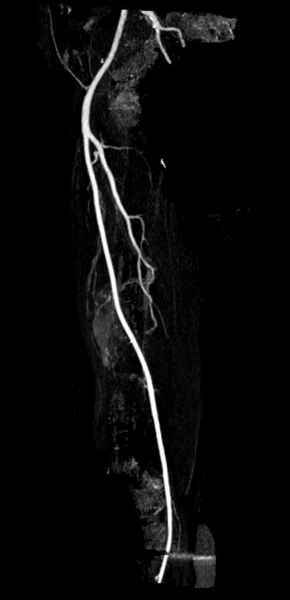

Для предупреждения кровотечения во время рассверливания, за день до операции провели эмболизацию сосудов питающий метастаз. http://radiology.rsnajnls.org/cgi/reprint/150/3/673.pdf (7-11, 12-15-16)